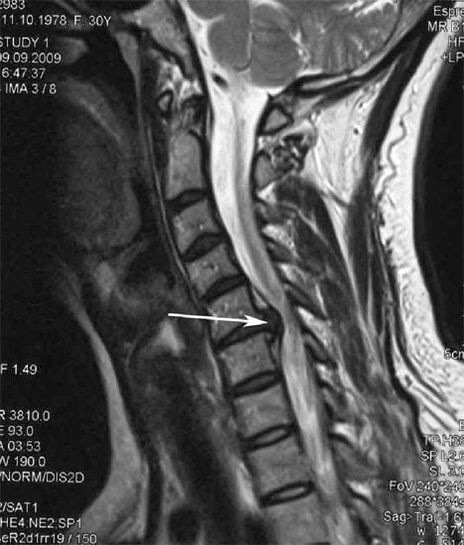

In the initial stages, osteochondrosis is detected using MRI.Later, the pathology can be diagnosed using radiographs.In radiographs of the cervical spine, a decrease in the distance between the vertebrae, pathological changes in the fascial joints and osteophytosis become visible.

Many people complain that they cannot turn their necks because of severe pain that occurs after suddenly lifting something heavy.This phenomenon indicates the formation of a disc herniation.The cause of pain in the back, neck and upper limbs is the compression of one of the nerve roots that come out of the spinal cord.